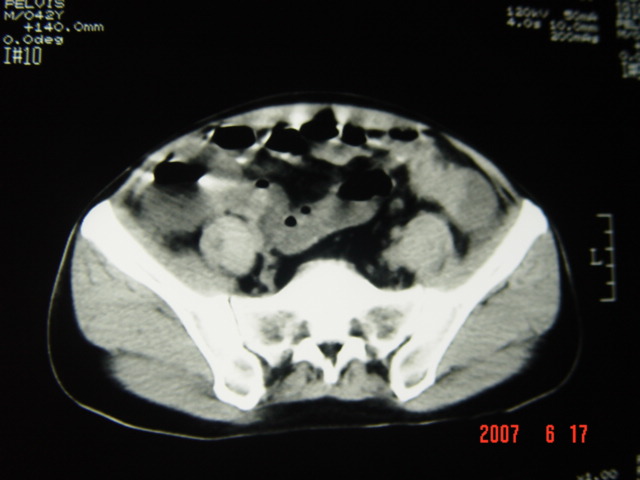

[br][br]以下是引用lkc8963在2007-6-17 13:32:00的发言:[br]完全支持邓主任意见:降/乙交界部占位性病变伴不全梗阻.做个增强或者be可能更好.